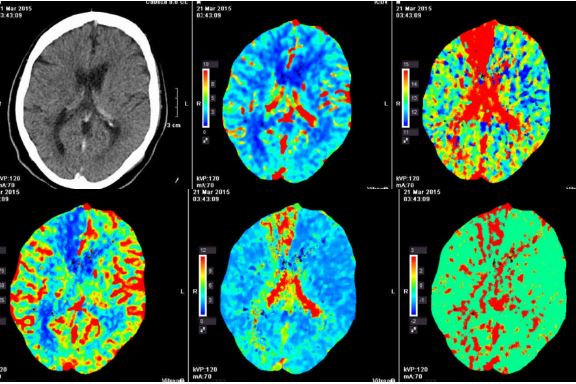

Revisión del tema

Se revisaron 214 estudios realizados en los últimos 9 meses por sospecha de ictus. De ellos un 30% presentaron alteraciones que no afectaban al territorio de la arteria cerebral media. Dividiremos los resultados en dos grandes grupos: aquellos con patología vascular (arteria cerebral anterior (fig. 1), arteria cerebral posterior (fig.2 y 3), infartos lacunares y trombosis de senos) y aquellos con patología no vascular (enfermedad desmielinizante, encefalitis, crisis convulsivas, vasoespasmo, vasculitis y patología tumoral). Un 17% presentó patología vascular mientras que en el 13% restante los hallazgos fueron concluyentes para patología no vascular. Dentro de este último grupo los diagnósticos más frecuentes fueron las crisis convulsivas, la fase de vasoespasmo de la migraña (pseudomigraña), la encefalitis y las enfermedades desmielinizantes. En los infartos lacunares (fig. 4) identificados el TC perfusión mostró un leve retraso en el tiempo al pico en región de ganglios basales con flujo y volumen conservados. La trombosis venosa puede presentarse con clínica ictal. En el estudio con TC perfusión suelen presentar un aumento del tiempo al pico con un volumen cerebral conservado en un territorio vascular venoso (fig. 5). La trombosis venosa puede presentar trastorno de perfusion sin infarto o asociarse a un infarto venoso; en esa circunstancia, los hallazgos en la TC de perfusión son los mismos que en el infarto arterial . Los pacientes con estado epiléptico no convulsivo muestran un aumento del metabolismo focal que en la TC de perfusión se manifiesta como un aumento del flujo sanguíneo cerebral, un volumen sanguíneo cerebral elevado, con un tiempo de drenaje, tiempo al pico y tiempo de tránsito medio disminuidos (fig. 6). Estos hallazgos pueden ser mal interpretados como hipoperfusión del hemisferio contralateral. Los pacientes con ataque epiléptico y parálisis postcrítica presentan un hipometabolismo focal cerebral de difícil diagnóstico diferencial con el ictus isquémico en ausencia de oclusión vascular. Los pacientes que presentan vasoespasmo pueden presentar un mapa de colores en el estudio con TC perfusión que simule un área de penumbra presentando un aumento del tiempo de tránsito medio y un flujo sanguineo cerebral conservado (fig. 7). Se debe estudiar con detenimiento la angioTC para valorar segmentos vasculares disminuidos de calibre. La vasculitis es una patología poco frecuente y de etiología desconocida. Presenta un cuadro clínico variable, de inicio subagudo a lo largo de semanas o meses, con frecuentes cefaleas, cambios del estado mental y déficits neurológicos focales y/o difusos; así como ictus por

alteraciones vasculares (estenosis, oclusión y aneurismas). En la TC perfusión se pueden identificar signos de hipoperfusión tisular, con aumento del tiempo de tránsito medio , con posible disminución del volumen sanguíneo cerebral con subsiguiente isquemia y pérdida de viabilidad tisular. Los pacientes con cuadros de encefalitis suelen presentar cuadros clínicos característicos como fiebre, convulsiones y focalidad neurológica. En ocasiones no resulta tan sencillo y el paciente puede encontrarse en coma haciendo el diagnóstico complejo. Estos pacientes presentan en el estudio de TC perfusión disminución del tiempo de tránsito medio y tiempo al pico con flujo y volumen conservados o disminuidos (fig. 8). Se puede interpretar erroneamente como afectación vascular ictal contralateral. Los estudio con TC perfusión ayudan al diagnóstico de patología vascular más allá del territorio de la arteria cerebral media y de patología no vascular a veces no sospechada al ingreso reorientando al clínico a la hora de tomar decisiones terapeúticas. El radiólogo de urgencias debe estar familiarizado con los hallazgos en la TC perfusión de aquella patología que puede simular clínicamente un ictus.